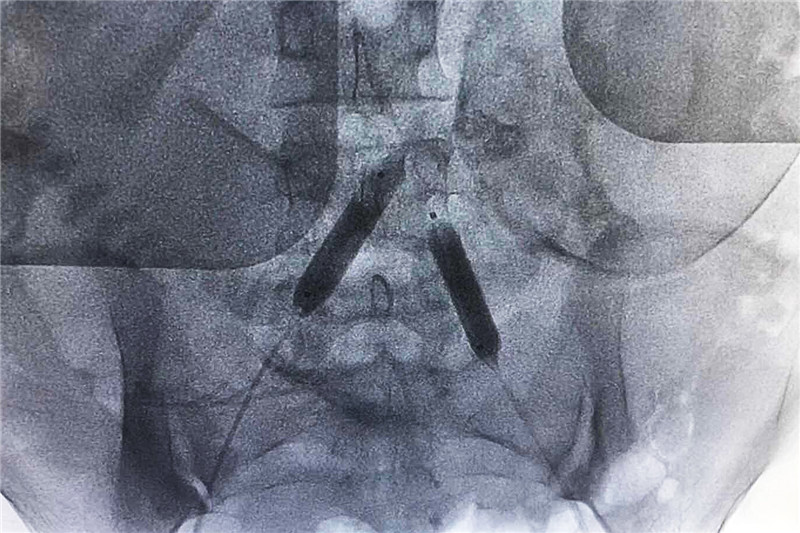

【DSA下预置球囊造影】

当晚七时许,小刘被送入DSA导管室,顺利在双侧髂总动脉置入球囊导管,随后接受剖宫产术。

影像科副主任郑胜介绍,髂总动脉球囊预置术通过介入技术,阻断髂内动脉及子宫的主要血供,可以减慢出血速度,有利于创面凝血,将减少子宫出血。同时,出血减慢可以充分暴露胎盘剥离面出血点,手术视野清晰,有助于术者进行胎盘剥离、缝合等操作。